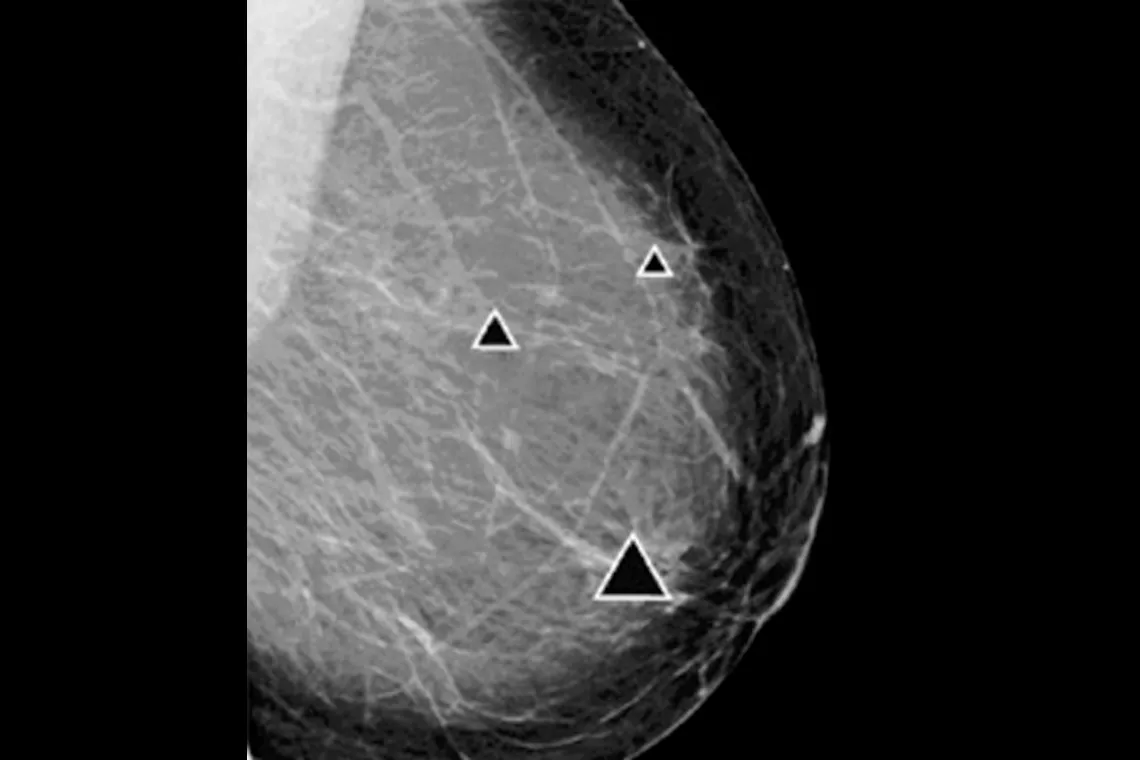

ImageChecker 2D CAD Technology searches digital mammograms for potential microcalcifications and masses, characteristics commonly associated with breast cancer.

• Regions-of-interest are highlighted for the radiologist’s attention

• Delivers highly sensitive results without excessive false-positive marks, streamlining case review2

Digital mammography with peer emphasize marks